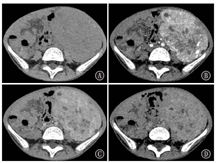

CT平扫上可见肿瘤呈不均匀等/低于肌肉密度,其中3例肿瘤于中心区域可观察到斑片样低密度区,2例低密度区呈小灶状或条片状散在分布,增强后不强化或仅呈轻度强化,CT值升高均<10 HU,病变周围部分可见动脉期明显强化,CT值升高约30~79 HU,静脉期呈持续强化,CT值继续升高8~36 HU,2例肾脏病变者加做了延迟期扫描,可见病变周围部分有强化减低表现,1例出现向心性强化(图1)。1例病变平扫密度较均匀,未观察到明显密度减低区,增强后病灶仍以周边强化为主,CT值升高约52 HU,中心区域轻度强化(CT值升高约17 HU)呈相对低密度区。5例肿瘤内可见迂曲增粗血管影,且多分布在肿瘤周边部分(图2)。2例病灶内可见点状及沙砾样钙化。

在增强CT图像中,PEComa常在动脉期表现出周边分布的明显强化,这表明PEComa是一种富血管性肿瘤,且供血微血管常围绕肿瘤周围存在,这一"周边强化"的影像学特征可能对PEComa的鉴别诊断很有价值[3,11]。由于病变内拥有多种不同的细胞成分,故多呈不均匀强化,5例肿瘤中心的低密度不强化区代表了瘤内的大面积坏死、液化部分,其中3例肿瘤切除后得到了病理证实。1例病变平扫密度较均匀,增强后仍以周边强化为主,中心区域轻度强化呈相对低密度区,可能与其平滑肌结构或其他少血管成分有关。对本组病例的CT动脉期图像进行最大密度投影(MIP)重建可清晰显示肿瘤内迂曲增粗的血管,可见5例PEComa的血管分布于病变边缘,呈包绕状,这与大多数肿瘤血管常延伸至病变内有所不同。静脉期多数PEComa在静脉期呈持续强化,延迟期病变周围部分出现强化减低,1例病变出现类似"血管瘤"的向心性强化,更说明了该病变血供丰富。